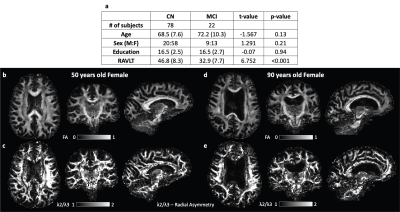

本研究深入分析了磁共振弥散张量成像(MR-DTI)中的径向不对称性,并探讨了其对脑脊液循环机制理解的影响。研究者提出了两个假设:一是MR-DTI能够揭示白质纤维束中显著的径向不对称性;二是这种不对称性(A2/A3比率)在神经退行性病变中会普遍下降,不依赖于纤维的方向性。

实验涉及78名认知功能正常的参与者与22名轻度认知障碍(MCI)患者。我们利用MR-DTI技术,重点关注白质纤维束内的A2/A3比率,并将其与认知功能(通过Rey听觉语言学习测试评估)进行了关联。结果表明,相较于健康对照组,MCI组在特定白质纤维束中A2/A3比率显著降低,暗示径向不对称性的减少可能与神经退行性病变相关。此外,A2/A3比率与认知功能下降之间存在关联。

综上所述,MR-DTI中的径向不对称性对于评估和理解脑脊液循环及相关神经退行性疾病具有重要意义。

e0baac63fa578bfe8370a28176aa01ad.png

参与者的人口统计学特征以及两个代表性受试者的FA(各向异性分数)和λ2/λ3(弥散张量特征值比率)图。

(a) 人口统计学和认知特征包括每个组的平均值(标准差)。

(b) 一名50岁女性的FA图和径向不对称性图

(d) 一名90岁女性的FA图和径向不对称性图。

这些图表明,无论是50岁还是90岁的女性,都存在径向扩散不对称性。